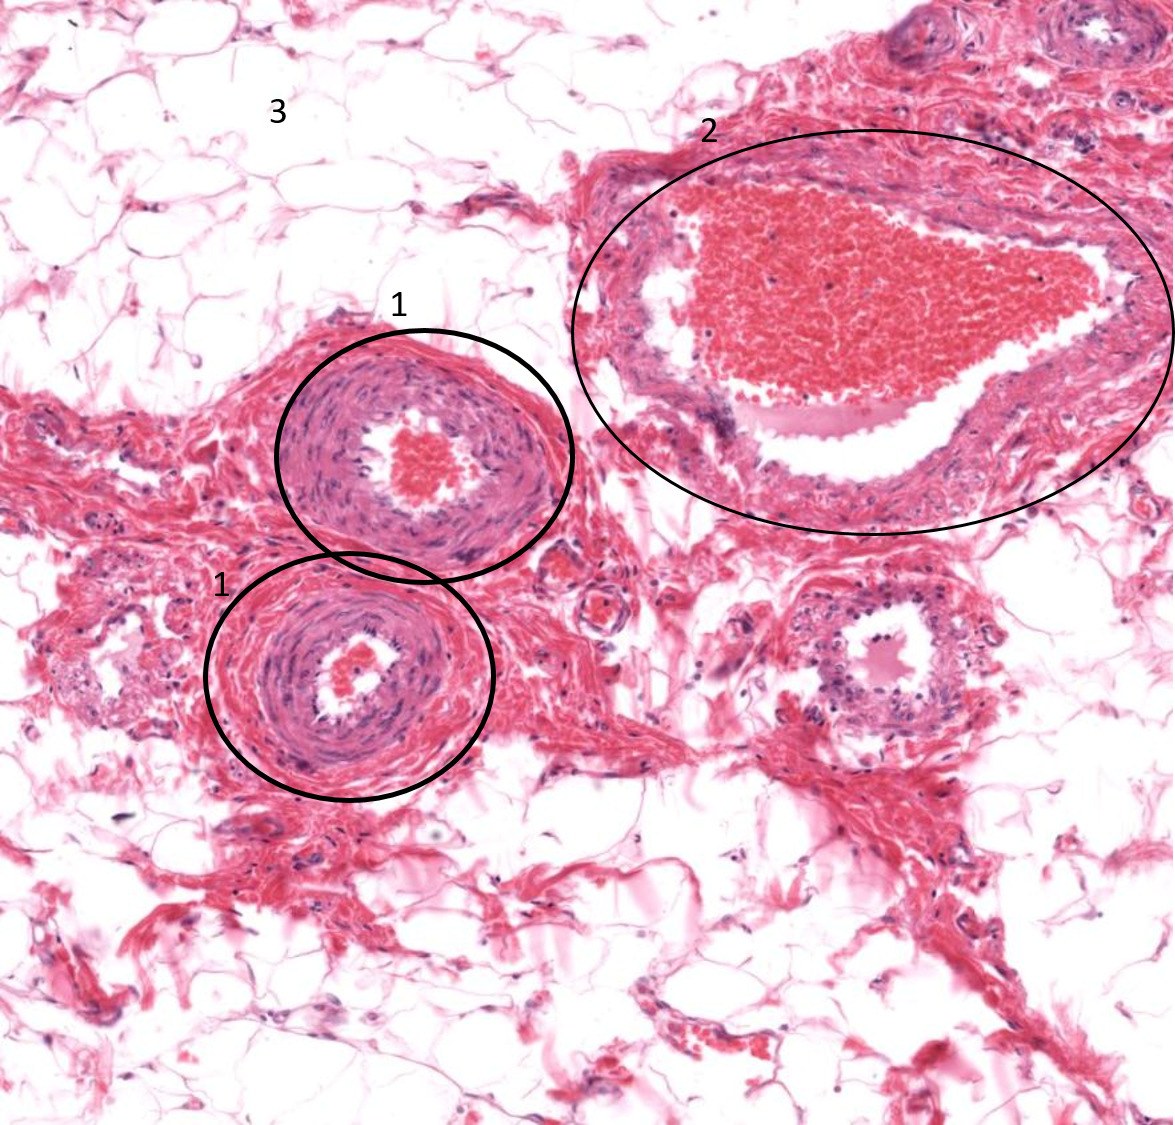

1: Artéria

2: Veia